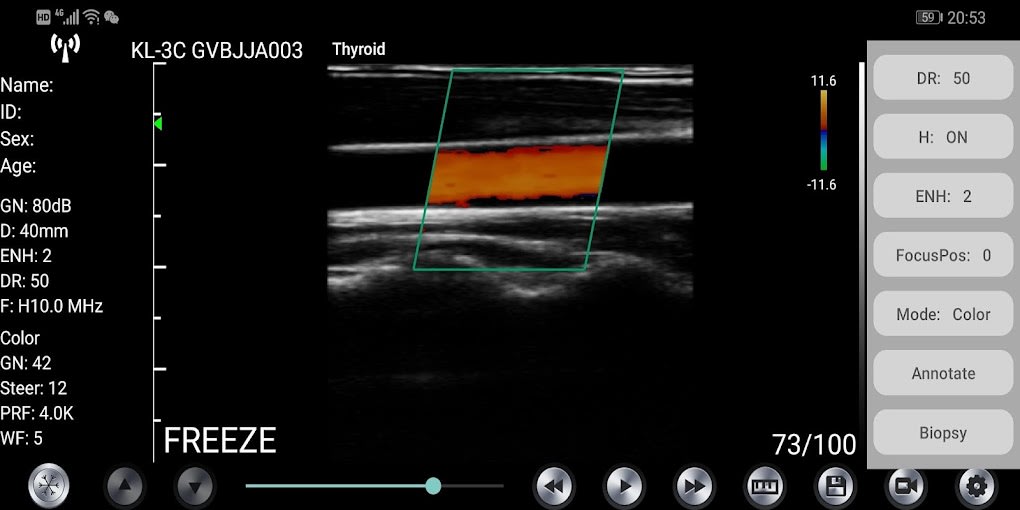

WirelessKUS is a free medical ultrasound transducer app developed by kontedmed for Android devices. It allows the user to establish a wireless connection between the ultrasound transducer and their smartphone or tablet via WiFi. The app offers a range of features such as patient information management, gain adjustment, depth control, frequency adjustment, dynamic range adjustment, image area control, freeze/live status, gain adjust button, measurement tools, image and video saving options, WIFI channel selection, puncture guidance, comment adding, image model selection, focus position adjustment, ENH enhancement, THI on/off, and dynamic range control.

To connect the ultrasound transducer with the app, the user must enter the WiFi password for the first time, which is the serial number of the probe in small letters. After the first-time connection, the app will automatically connect with the probe's WiFi. The software interface displays the probe's status, and the user can adjust the settings using the various options available. The app also allows the user to fine-tune the location of the measuring point and delete all the measurement results with a single click.